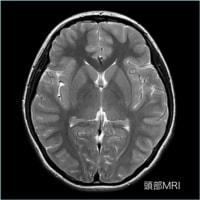

軟部組織のコントラストに優れ、様々なコントラストパラメーターを有するMRIは、頭頚部、体幹部、脊椎・脊髄、整形領域、心臓領域とほぼ全身に渡る断層画像をあらゆる角度で撮像できます。

MRIの画像